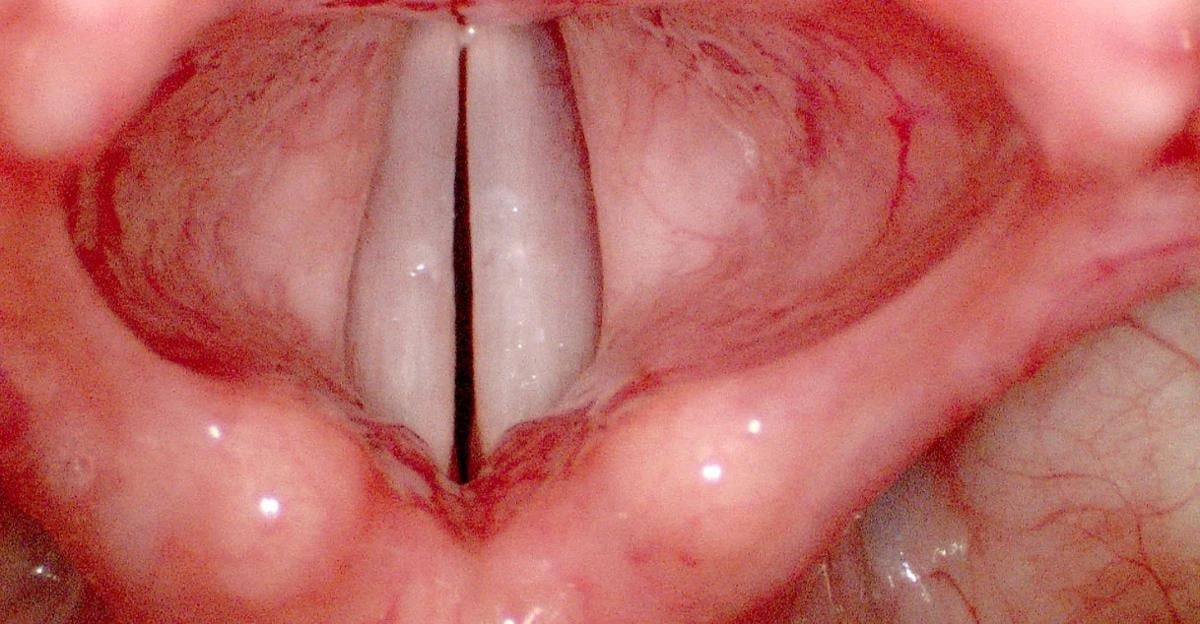

Ses telleri, boğazda gırtlak kısmında yer alır. Ses teli denilince gerçekten tele benzetenler olacaktır ancak görüntüsü oldukça farklı.

Sesimizin çıkmasını sağlayan ses tellerini gören şaşkınlık yaşıyor.

Peki siz hiç merak ettiniz mi? Bakın ses telleri nasıl görünüyor...

Gırtlakta yer alan ses telleri, hem sağ hem sol taraftan, oldukça ince bir ciltle sarmalanmış, kas lifleri ve yumuşak doku içeren oluşumlardır. Zarımsı bir yapıdadır.